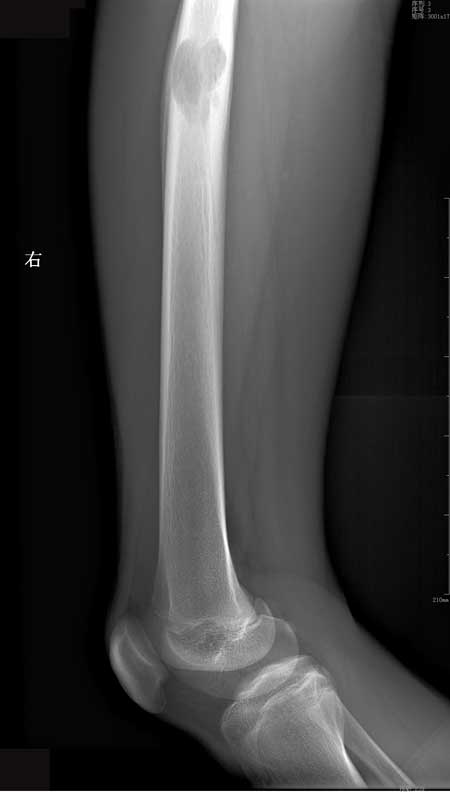

右股骨干嗜酸性肉芽肿

M23岁,右侧大腿疼痛两月余,无其他~~~

【zxl51642】良性肿瘤样病变,考虑Langerhands组织细胞增生症(嗜酸性肉芽肿)。

【ZHANGZHONGSHOU】嗜酸性肉芽肿可能性大,囊状骨质破坏,累及骨皮质,骨膜增生、骨皮质增厚,连续、无破坏,范围常于骨破坏范围,患者青年均支持嗜酸性肉芽肿可能性大。

【黑白光影】好发的年龄,孤立而界限分明的溶骨性缺损,偏于一侧的骨膜反应,考虑嗜酸性肉芽肿可能性大。

【wudaodong2008 】骨髓腔反应范围较大界限模糊、皮质增厚广泛 骨膜反应明显但层次不清-----符合炎性改变;瘤子不考虑。

病理报告:(右股骨中上段肿物)符合嗜酸性肉芽肿